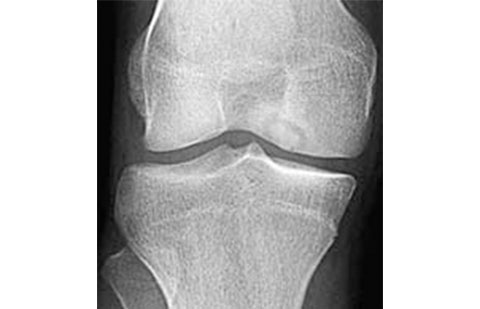

Os exames de imagem são de grande valia para o diagnóstico da fratura por fadiga ou síndrome da insuficiência do joelho. A ressonância é o exame que mais auxilia neste diagnóstico.